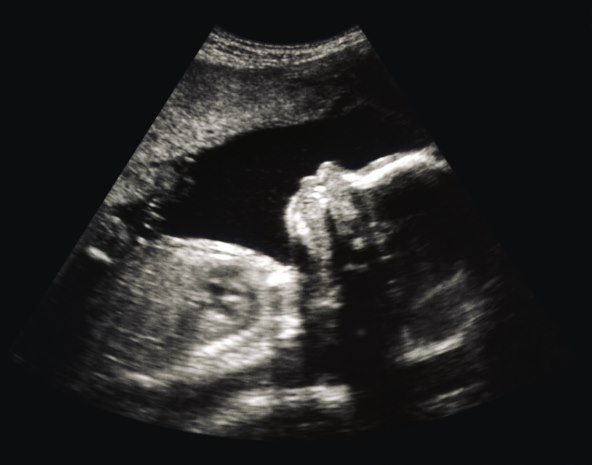

1. Ultrazvuk

To je neinvazivan način određivanja spola djeteta i obično se radi između 18. i 22. tjedna trudnoće. Ultrazvuk možda neće uvijek otkriti spol ako bebina pozicija nije idealna ili ako je prerano za određivanje spola djeteta. U tim slučajevima možda ćete pregled morati ponoviti.